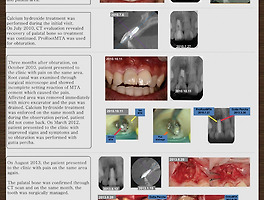

| OrthoMTA를 활용한 성공적인 재근관치료 : MTA 신경치료 근관충전 (0) | 2014.12.13 |

| MTA 근관충전의 성공률 Orthograde MTA filling, MTA total filling (0) | 2014.12.13 |